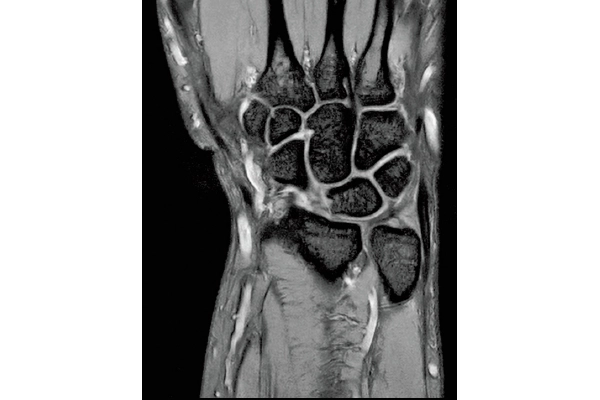

T2*WI Multi Echo,

0.38×0.38×2.0mm

0.35×0.40×3.0mm, 2:55

3D Bone

0.93×0.93×1.2(0.6)mm

1.1×1.1×1.2(0.6)mm